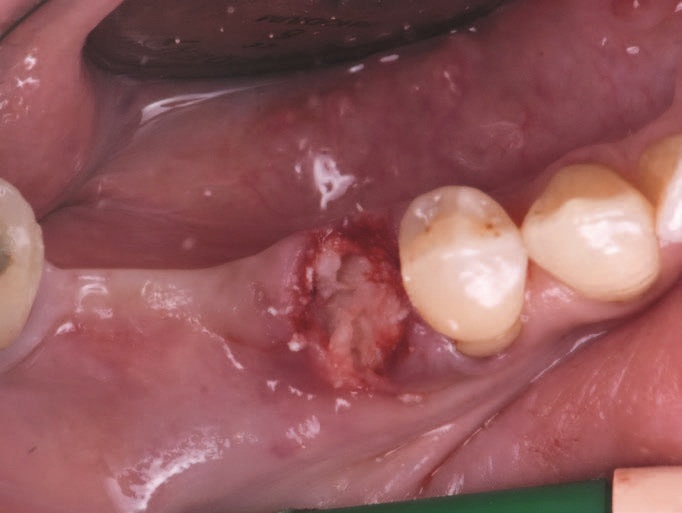

Рис. 2 – Клиническое обследование - наблюдается металлокерамический мост, включающий реабилитационные позиции от 4.5 до 4.8.

Рис. 4 – Пост-экстрационная лунка.

Пациент обратился к хирургу с мостом в правой задней дуге для реабилитации зубов с 4.5 до 4.8 включительно. Зуб 4.5 показал кариес корня, что сделало его непригодным для поддержки мостика. Затем было запланировано удаление зуба 4.5, а также выполнение процедуры сохранения гребня на постекстрационной лунке для того, чтобы в будущем осуществить протезирование на имплантатах.

Пациент прошел обычную антибиотикопрофилактику, а старый протез был удален путем мезиального отделения к зубу 4.8. Затем был удален зуб 4.5, и безлоскутно, лунку заполнили костной пастой Activabone без регидратации. При контакте с кровью костная паста впитывала ее и приобретала формовочную текстуру, что облегчало заполнения лунки.